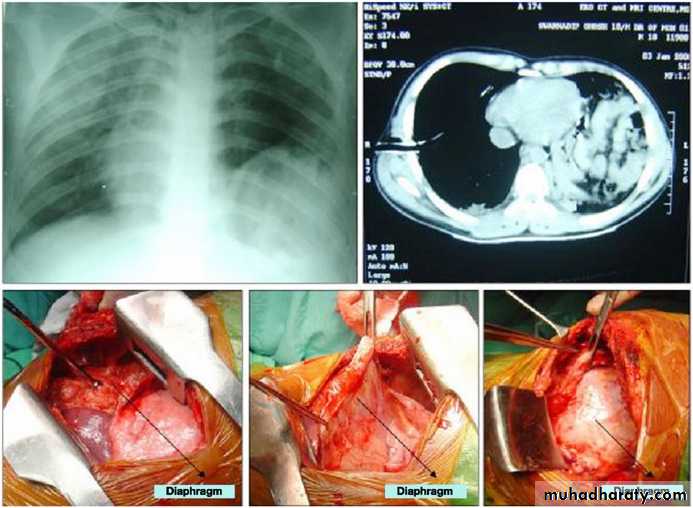

Diaphragmatic ruptureDiaphragmatic rupture

Diaphragmatic rupture

Liver herniation in right side